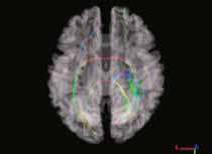

«Изменения коннектома головного мозга у пациентов с детским церебральным параличом в поздней резидуальной стадии при транслингвальной нейростимуляции». Обобщена МР-семиотика структурных и функциональных изменений головного мозга у детей со спастической диплегией. У детей с ДЦП в поздней резидуальной стадии преобладает снижение коннективности между компонентами сети выявления значимости и корой лобно-теменной области, компоненты которой также структурно связаны с компонентами сенсомоторной сети. При выполнении коннектометрического анализа трактов после ТЛНС (основная группа) выявлено повышение фракционной анизотропии более чем на 20 % (p < 0,001) в передней спайке (47 % от общего количества волокон), правом нижнем лобно-затылочном пучке (13 % волокон), левой поясной извилине (10 % волокон), правой зрительной лучистости (6,7 % волокон), мозолистом теле (6 % волокон), правой поясной извилине (1,3 %) (рисунок).

| Графическое представление результатов межгруппового статистического анализа: 2D-реконструкция проводящих путей белого вещества головного мозга с повышением ФА после ТЛНС в аксиальной (а), сагиттальной (б) и корональной (в) плоскостях. Показаны проводящие пути и часть их волокон, которые повысили ФА более чем на 20 % после комплексной реабилитации | ||

При выполнении коннектометрического анализа трактов после стандартной двигательной реабилитации (группа сравнении) статистически значимого повышения фракционной анизотропии (более чем на 20 %) не выявлено. При проведении диффузионной МРТ у детей с ДЦП в поздней резидуальной стадии выявлено статистически значимое снижение фракционной анизотропии в трактах белого вещества головного мозга, что свидетельствует о нарушении общих процессов миелинизации и, следовательно, скорости проведения нервных импульсов по их аксонам. Выявлены структурные и функциональные изменения головного мозга у пациентов с ДЦП после ТЛНС, которые свидетельствуют об усилении активации процессов нейропластичности.